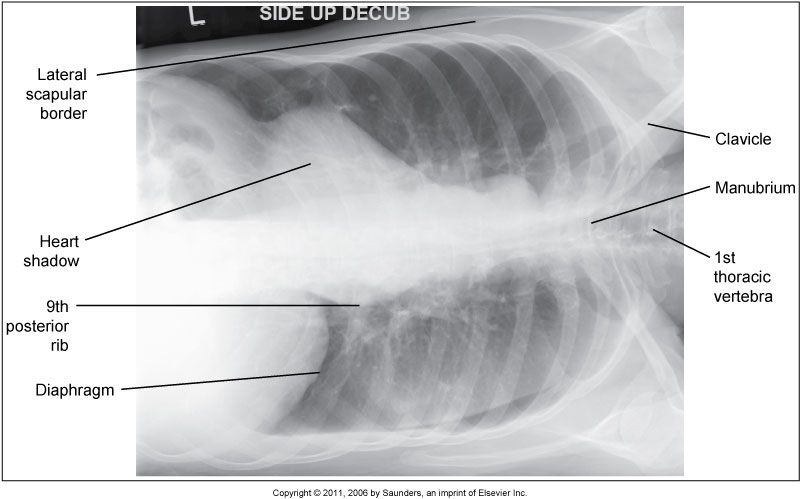

What position is demonstrated?

Right Lateral Decubitus Chest